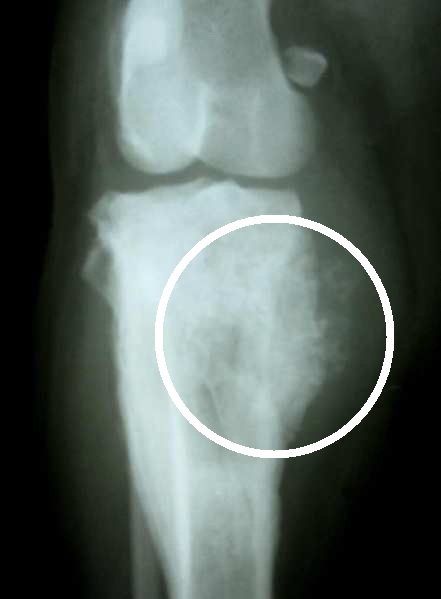

Knochentumor beim Meerschweinchen

Knochentumor beim Hund